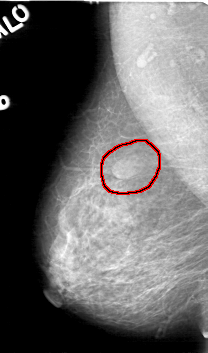

FILE: D_4046_1.RIGHT_CC.OVERLAY

TOTAL_ABNORMALITIES 1

ABNORMALITY 1

LESION_TYPE MASS SHAPE OVAL MARGINS OBSCURED

ASSESSMENT 0

SUBTLETY 4

PATHOLOGY BENIGN

TOTAL_OUTLINES 2

BOUNDARY

RIGHT_CC LINES 5221 PIXELS_PER_LINE 2971 BITS_PER_PIXEL 12 RESOLUTION 43.5 OVERLAY